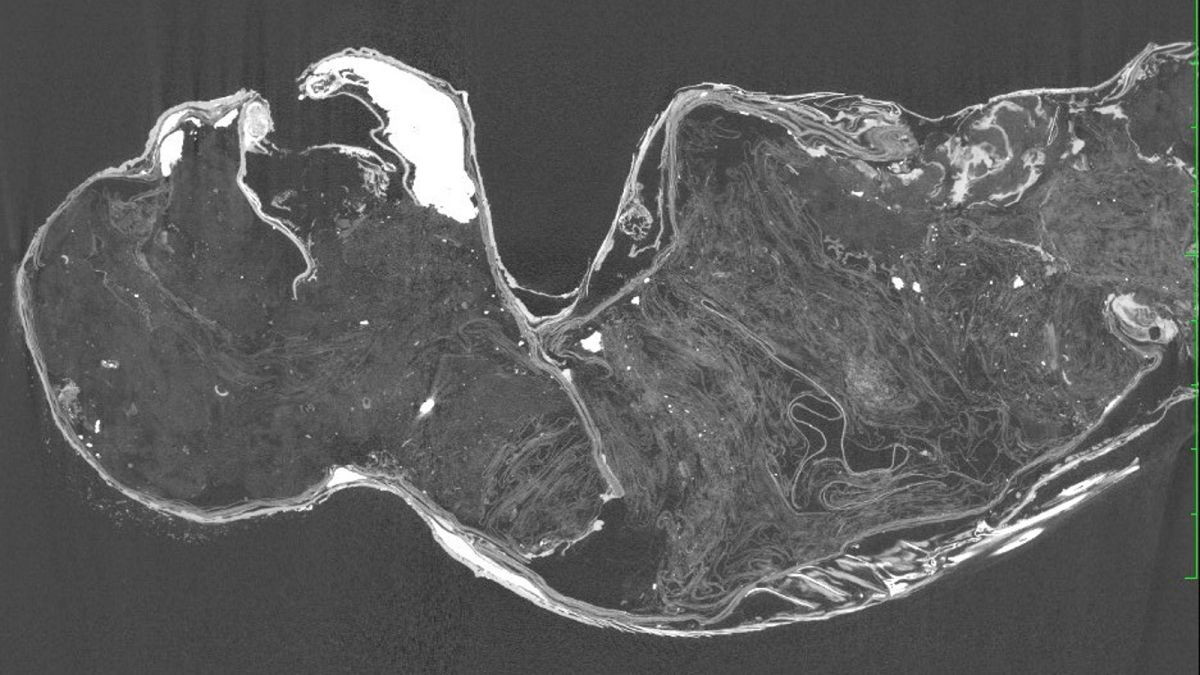

Ảnh quét CT xác ướp "nàng tiên cá" - Ảnh: KUSA

Trong bản báo cáo mới, các nhà khoa học từ Trường Đại học Khoa học và nghệ thuật Kurashiki (KUSA - Nhật Bản) cho biết "nàng tiên cá" là một hỗn hợp của nhiều động vật, vải giấy, bông, cát, than củi, kim loại.

Cụ thể, phần thân của nàng tiên cá không phải của khỉ mà chủ yếu làm từ vải giấy và bông được giữ với nhau bằng các chốt kim loại chạy từ cổ xuống lưng, được sơn bằng hỗn hợp chứa cát và than củi.

Tuy nhiên, phần thân này cũng được bao phủ một cách tinh vi bằng những bộ phận tước từ nhiều động vật khác nhau: Lông từ động vật có vú, da cá (có thể là cá nóc) bao phủ cánh tay, vai, cổ và má; hàm và răng có thể từ một loài cá săn mồi; móng lấy từ một động vật chưa xác định.

Nửa dưới của "nàng tiên cá" thì đúng là một loài cá, rất có thể thuộc nhóm cá lù đù.